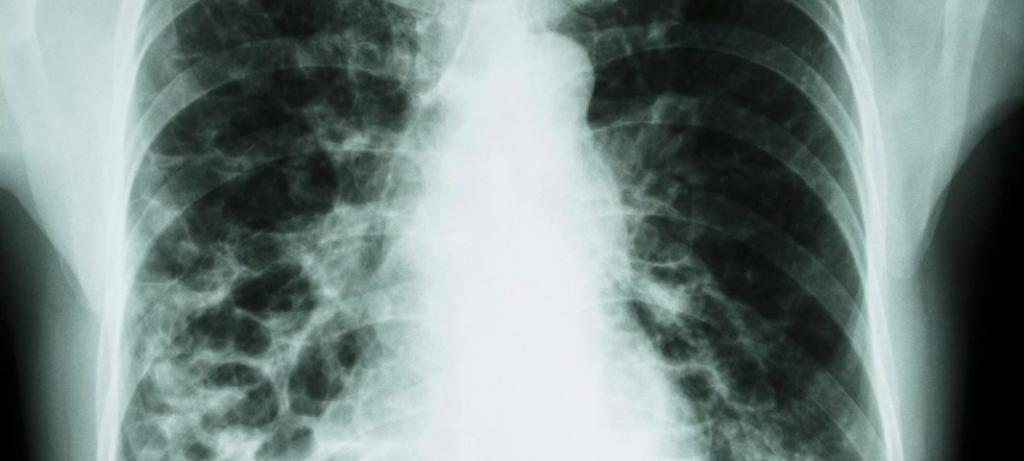

According to statistics, the average dose that people receive from natural sources is about 2.2-3.6 mSv, which is many times higher than the equivalent doses received during fluorography.Therefore, this diagnostic study itself, as a way of annual diagnosis, cannot cause significant harm to the body. However, taking into account the radiation background and the need to use other methods of x-ray studies, some risk is still present, but such risks are significantly lower than those due to the occurrence of hidden forms of the pathological process.